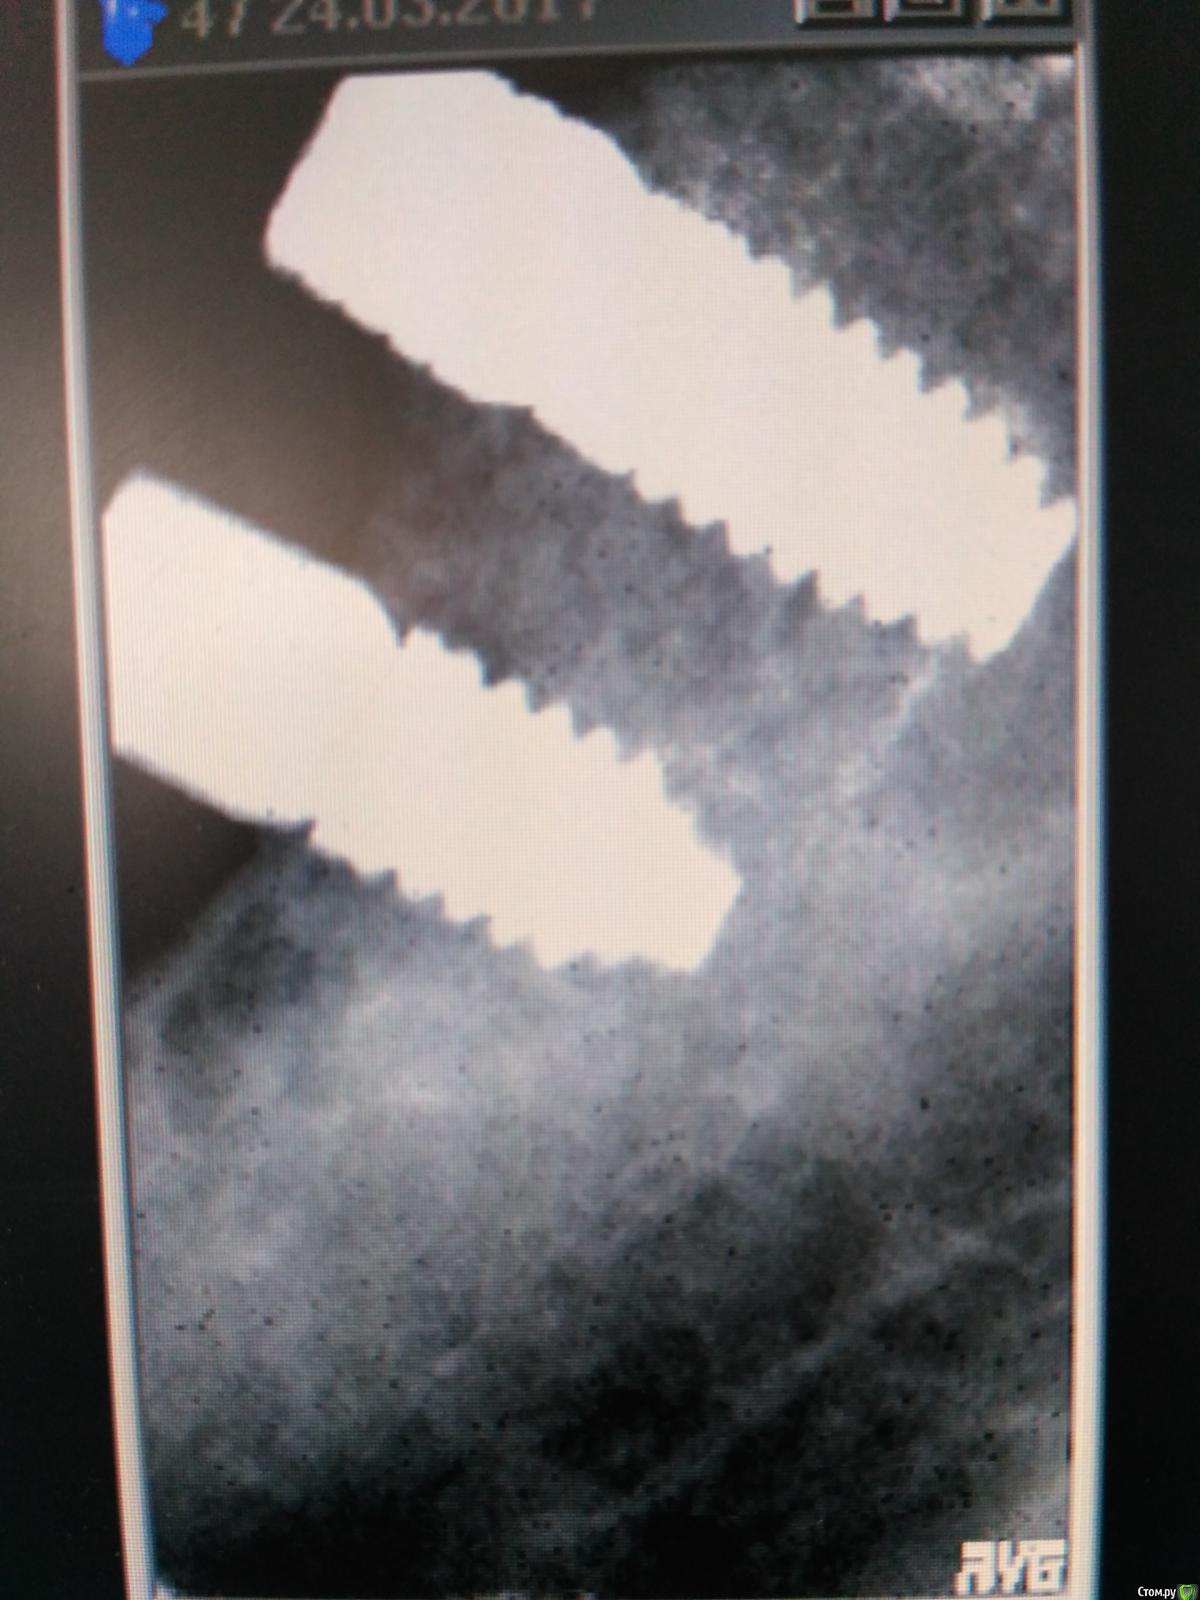

Пациент с жалобами на отсутствие 47 разрушение 46,48. После совещания с ортопедом и терапевтом принято решение удалять 46,48 и устанавливать импланты в позицию 46,47. post-48560-0-74269200-1490419709_thumb.jpgpost-48560-0-43642200-1490419772_thumb.jpgПрисутствует парадонтоз, лечение у пародонтолога прошел заранее. Решено было 46 ставить одномоментно, с графтом и мембранкой, 47 по стандартному протоколу, импланты alpha bio aic 4,2*12, 4,2*10 соответственно. post-48560-0-27512000-1490420040_thumb.jpgpost-48560-0-53003700-1490420066_thumb.jpg Сначала удалил, атравматично с распилом по бифуркации.post-48560-0-43340000-1490420143_thumb.jpgpost-48560-0-35881400-1490420170_thumb.jpgРаскрылся над 47, подготовил ложе, пины параллельности. Здесь вопрос, думаю зря широко отслоился и затронул 46?post-48560-0-32979400-1490420293_thumb.jpgpost-48560-0-94312700-1490420324_thumb.jpgустановка имплантов с фдм, графт в лунки 46 апатос, мембрана Эва. Снять не получилось. Нить моно 5-0. Тут опять вопрос фдм нужно было ставить шире? Но опять же импланты заглубил немного...post-48560-0-50977700-1490420493_thumb.jpg и контрольный. Конструктивная критика приветствуется)))